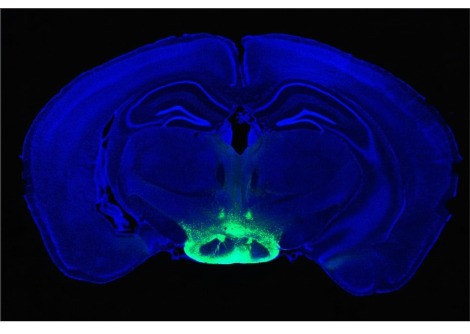

أظهرت دراسة جديدة أن اللوزة الدماغية (Amygdala) التي تعاني من الإجهاد المزمن يمكن أن تحفز القلب على المبالغة في رد الفعل تجاه أحداث الإجهاد الحاد.

أظهر العمل السابق أن مرضى TTS لديهم نشاط مرتفع في اللوزة الدماغية ، وهي منطقة دماغية تشارك في الاستجابة للضغط. لكن ما لم يكن واضحًا أبدًا هو ما إذا كان "هذا النشاط في الدماغ يحدث نتيجة للمتلازمة أو ما إذا كان قد بدأ قبل سنوات عديدة" ، كما يقول شادي أبوهاشم ، اختصاصي أمراض القلب النووي في كلية الطب بجامعة هارفارد.

حلل أبو هاشم وزملاؤه بأثر رجعي فحوصات PET / CT لكامل الجسم من 104 مريضًا ، معظمهم مصابين بالسرطان و 41 منهم قد طوروا TTS منذ أن تم فحصهم لأول مرة ، و 63 عنصر تحكم مطابق بشكل فردي. قام الفريق بحساب نسب النشاط في اللوزة الدماغية لكل شخص إلى تلك الموجودة في منطقتين دماغيتين تعملان على إضعاف استجابة الإجهاد ، الفص الصدغي وقشرة الفص الجبهي . ارتبط نشاط اللوزة الأعلى بزيادة خطر الإصابة بمتلازمة  TTS، ومن بين المصابين بهذه الحالة ، كان المرضى الذين لديهم نسب أعلى قد طوروا TTS بعد التصوير , عامين تقريبًا  قبل أولئك الذين لديهم نسب أقل. يقول أبوهاشم: "يمكننا الآن أن نُظهر أن هذه المتلازمة تحدث نتيجة الإجهاد المزمن على مدى سنوات ، مما يجعل الشخص المتوتر عرضة للإصابة بالمتلازمة بسهولة أكبر وفي وقت أقرب من الأشخاص الأقل توترًا"